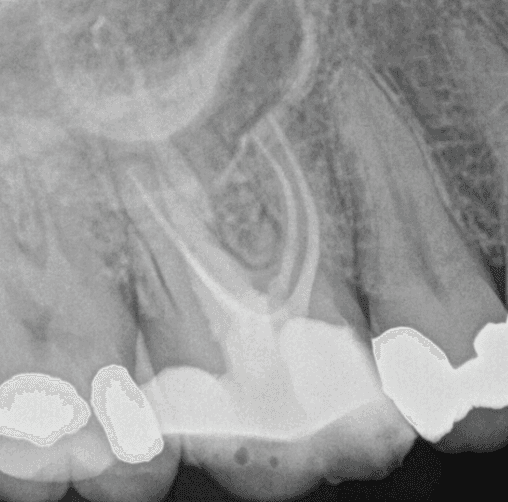

Your first visit is a specialist consultation with Dr Kreena Patel. We’ll take the time to understand your symptoms, assess any previous treatment, and carry out a detailed clinical and radiographic examination. A small digital X-ray is usually taken, and if needed, we may recommend a 3D CBCT scan to investigate further (additional fee).

A CBCT (cone beam CT) scan provides a detailed 3D image of your tooth and surrounding bone. It allows us to assess hidden canals, fractures, infection, or bone loss that are not always visible on regular X-rays.

This advanced imaging is especially helpful in complex or previously treated teeth, giving us the most accurate picture for diagnosis and treatment planning.